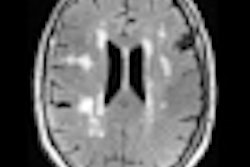

Researchers trying to develop better tools for predicting who will develop Alzheimer's disease used MRI to detect bright areas in the brain that indicate small-vessel cerebrovascular disease. The technique could be used with PET scans of beta-amyloid levels to predict Alzheimer's, according to a February 18 study in JAMA Neurology.

The group from Columbia University Medical Center believes that the bright areas, called white-matter hyperintensities, are signs of small-vessel cerebrovascular disease and part of the clinical presentation of Alzheimer's. Detection of the areas could offer additional information that complements PET scans of beta-amyloid levels, which aren't 100% certain in predicting which patients will eventually develop Alzheimer's.

The researchers then investigated the utility of MRI in the study group to compare the results with PiB-PET images. Because MRI can illustrate small-vessel cerebrovascular disease as brightly lit white-matter hyperintensities, the researchers collected T1-weighted, T2-weighted, and proton density MRI sequence information on the study participants.

MRI scans were acquired within six months of the PiB-PET images, and total white-matter hyperintensity (WMH) volume was calculated for each subject. The mean total WMH volume was 5.71 cm3 (median, 2.27 cm3), and total WMH volume did not differ between PiB-positive and PiB-negative individuals.